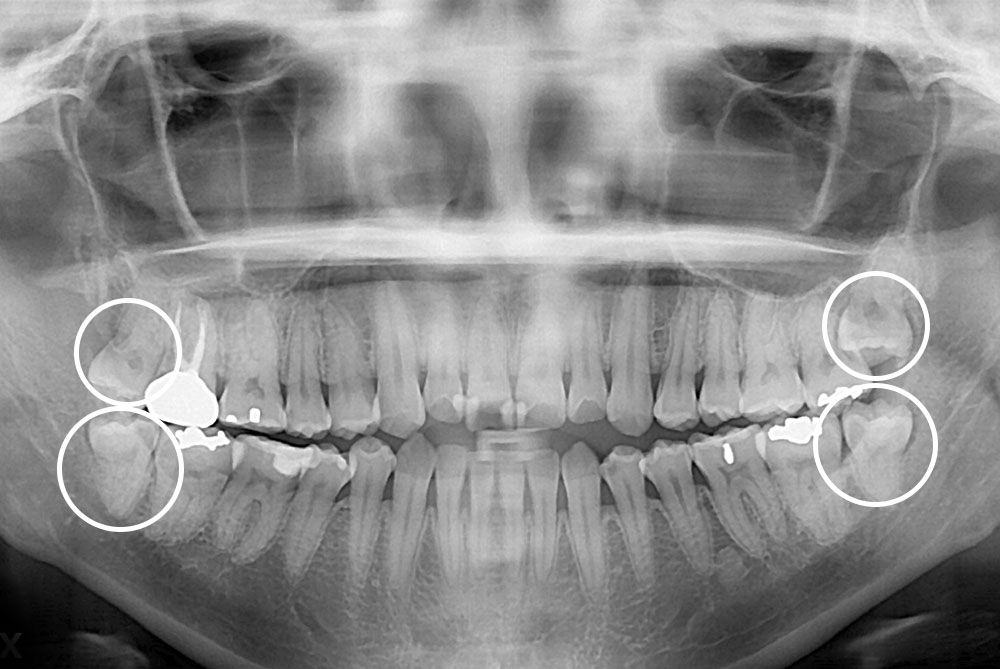

[사랑니] 매복 사랑니 발치

치료후 : 2019-01-11

세종치과는 구강악안면외과학 박사이신 원장님이 발치하는 치과입니다.